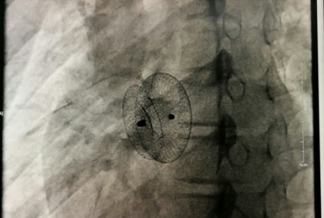

封堵器释放完毕

在征得患者及家属同意后,医院心血管内科手术团队在小章右侧大腿根部做了局部皮肤麻醉,穿刺股静脉成功后,经血管插入一根几毫米的导管,将封堵器送至缺损部位释放。术后立即做心脏彩超及心电图检查,证实无残余分流,无传导阻滞等并发症,手术成功。小章的先天性心脏病得到了“根治”,手术总共耗时约一个半小时。